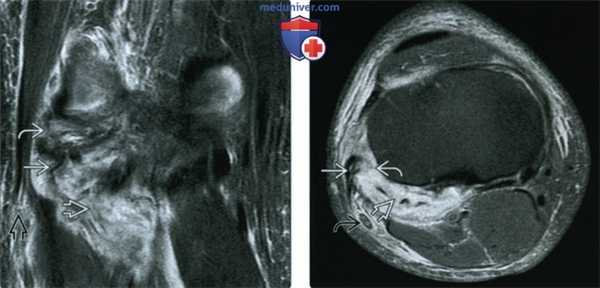

(Слева) MPT PDBИ, коронарный срез: определяется нормальная подколенно-малоберцовая связка (ПМБС). ПМБС идет от подколенного сухожильно-мышечного сочленения до места прикрепления к шиловидному отростку малоберцовой кости. Обратите внимание на нормальную подколенную мышцу и ДМБ. Визуализируется часть косой подколенной связки, которая обычно так не выступает.

(Справа) MPT PDBИ, режим подавления сигнала от жира, коронарный срез: определяется обширный отек и неровность волокон внутри ПМБС, характерные для разрыва тяжелой степени.

(Слева) МРТ Т2ВИ, режим подавления сигнала от жира, коронарный срез: определяется травма заднебокового угла тяжелой степени с разрывом подколенно-сухожильно-мышечного сочленения, ПМБС и комплекса дугообразной связки. ДБМ частично разорвана в дистальном отделе.

(Справа) MPT PDBИ, режим подавления сигнала от жира, аксиальный срез: у этого же пациента определяется заметный отек подколенной мышцы и комплекса дугообразной связки. Объединенное сухожилие остается неповрежденным. Малоберцовый нерв ЕЯ окружен отеком.